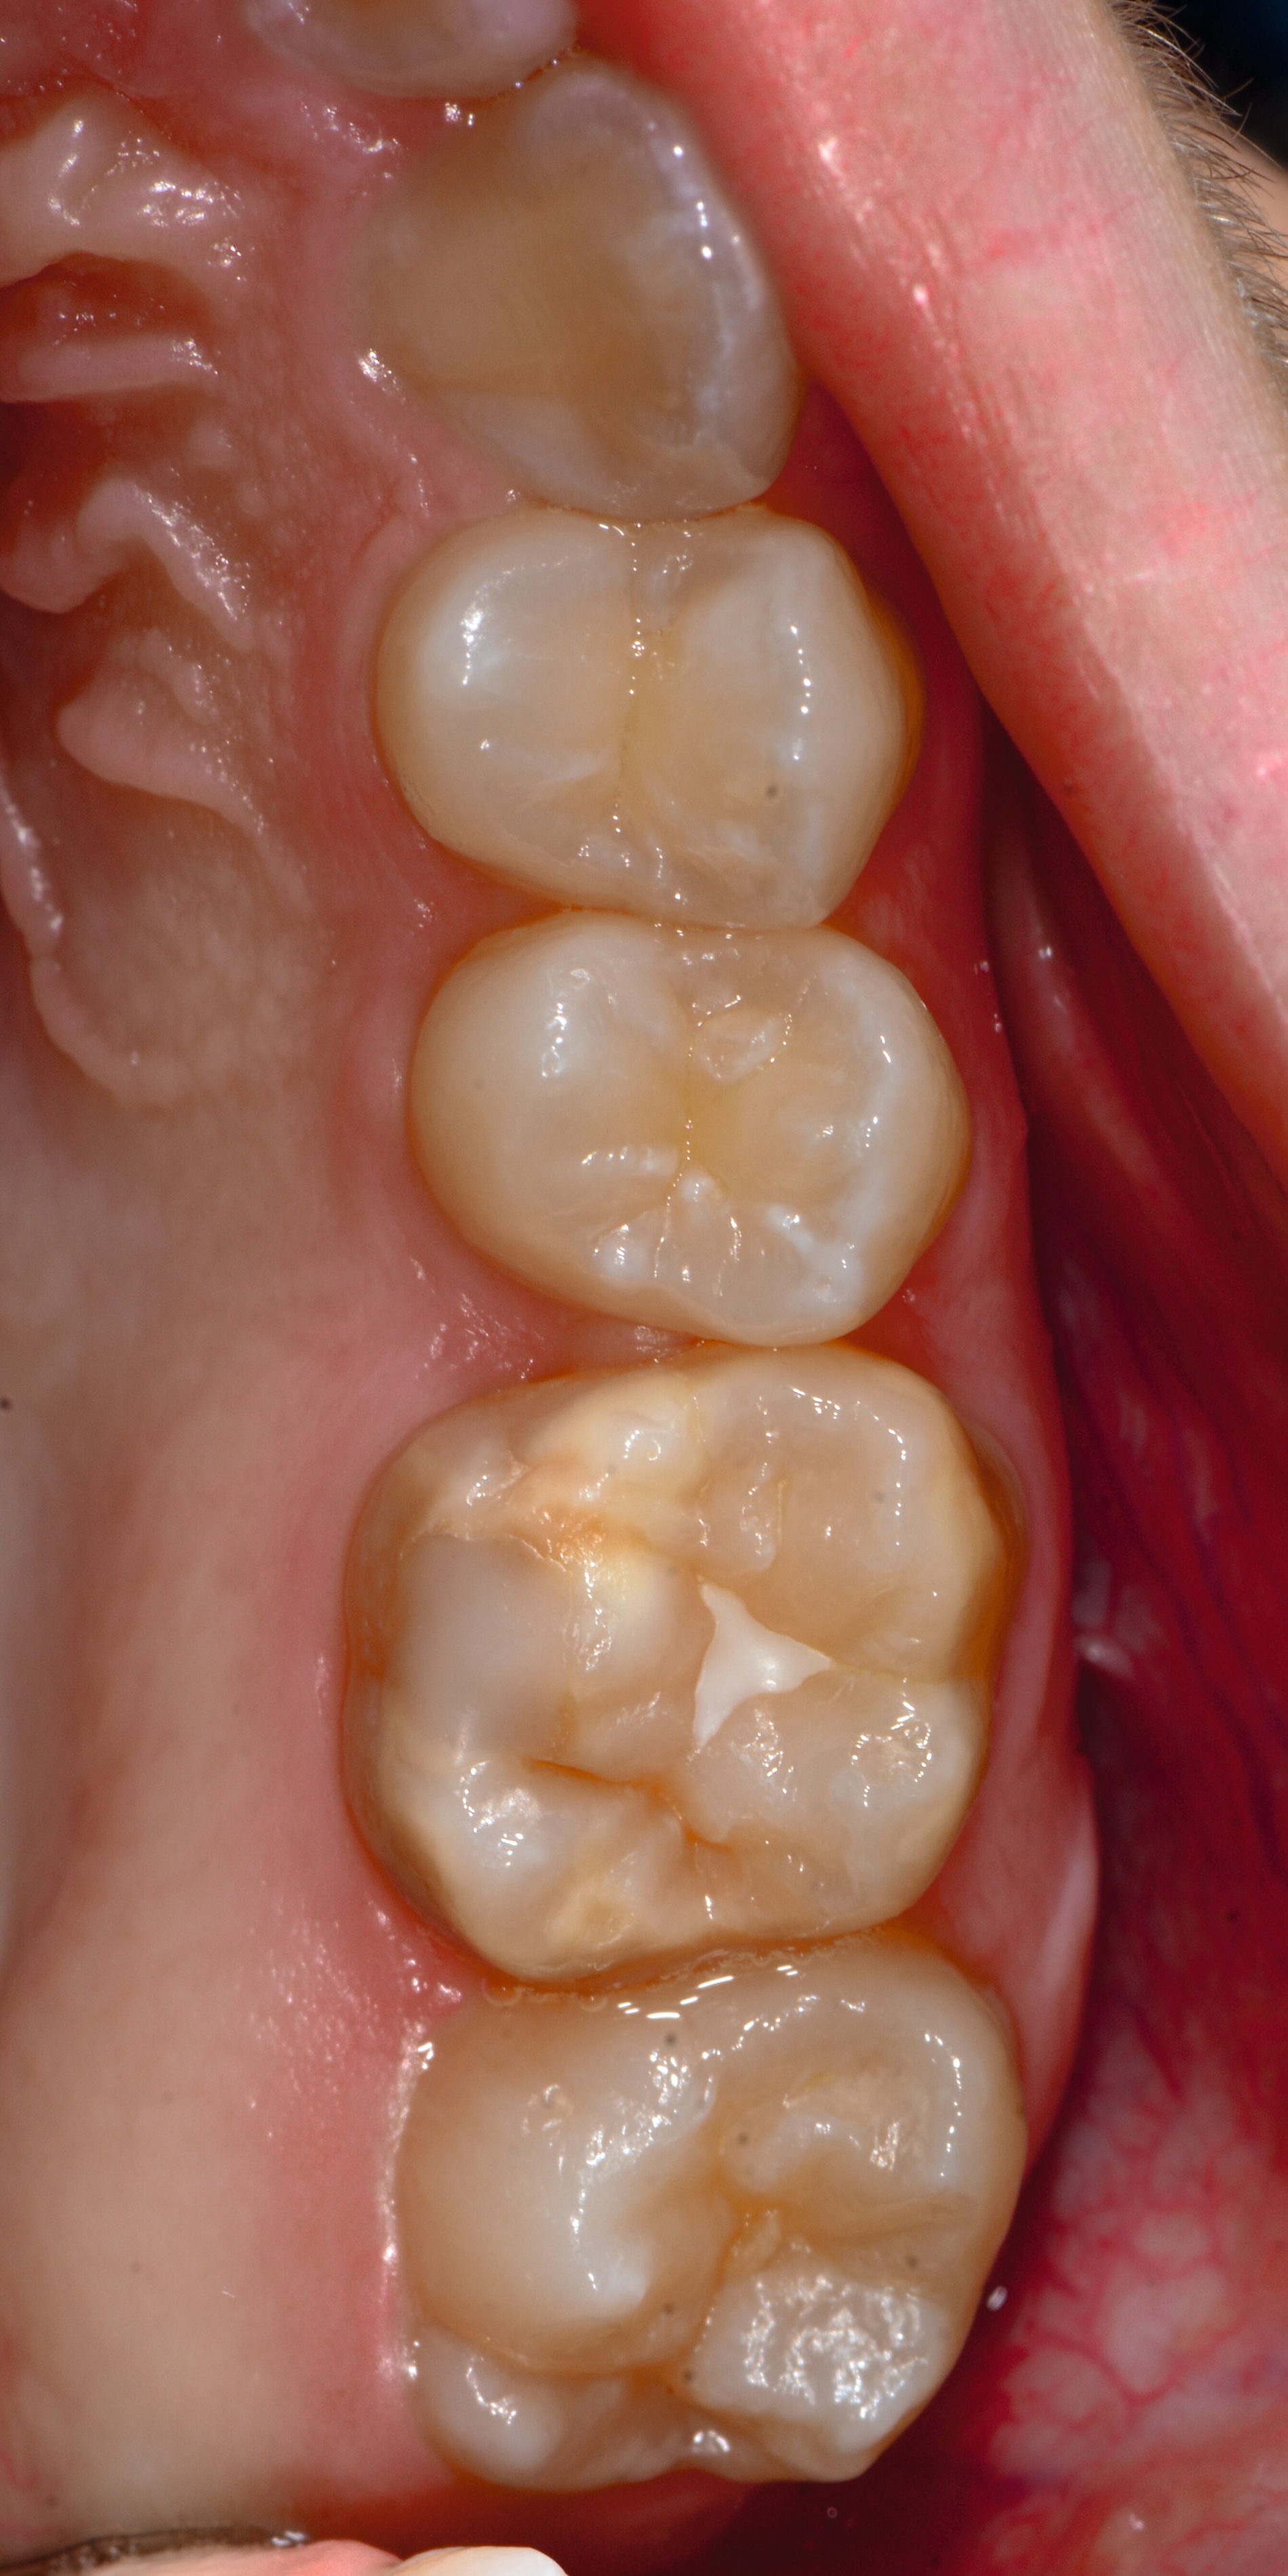

Das klinische Erscheinungsbild an bleibenden Zähnen zeigt typischerweise weißlich-gelbe bis gelblich-braune Opazitäten, die zumindest in einigen Bereichen durch eine scharfe Abgrenzung (engl.:„demarcated opacities“) zum gesunden Zahnschmelz charakterisiert sind (Abbildungen 3 und 4). Die abgegrenzten Hypomineralisationen befinden sich mehrheitlich im Bereich der inzisalen Kronenhälfte unabhängig von dem Auftreten an Front- oder Seitenzähnen. Die Ausprägung am Zahn kann dabei auf einzelne Areale oder Höcker begrenzt sein.

Bei einer schwerwiegenderen Ausprägung sind Zahnflächen vollständig betroffen, mitunter alle Zahnflächen an einem Zahn. Die Verteilung in der Dentition beziehungsweise an den Indexzähnen ist gleichermaßen variabel und betrifft nicht nur die Defektgröße, sondern auch die Farbe und Festigkeit. Was die Festigkeit betrifft, gilt als die Faustregel: Je dunkler die Farbe des Schmelzes, umso weicher beziehungsweise poröser und damit minderwertiger wird dessen Qualität sein. Damit reduziert sich seine kaufunktionelle Belastungsfähigkeit, was insbesondere an ersten bleibenden Molaren von klinischer Relevanz ist.

Für die Dokumentation und Klassifikation der MIH wurden verschiedene Systeme vorgeschlagen. Als historisch und veraltet gilt der (modifizierte) DDE-Index. Demgegenüber haben die Kriterien der EAPD – abgegrenzte Opazitäten (Abbildung 3 und 4), Schmelzeinbrüche (Abbildung 5), atypische Restaurationen (Abbildung 6) – mittlerweile die weiteste Verbreitung gefunden. Diese wurden 2003 erstmals zur Beschreibung der MIH auf empirischer Basis publiziert [Weerheijm et al., 2003] und den Jahren 2010 und 2022 im Rahmen der damaligen MIH-Workshops bestätigt [Lygidakis et al., 2010; 2022].